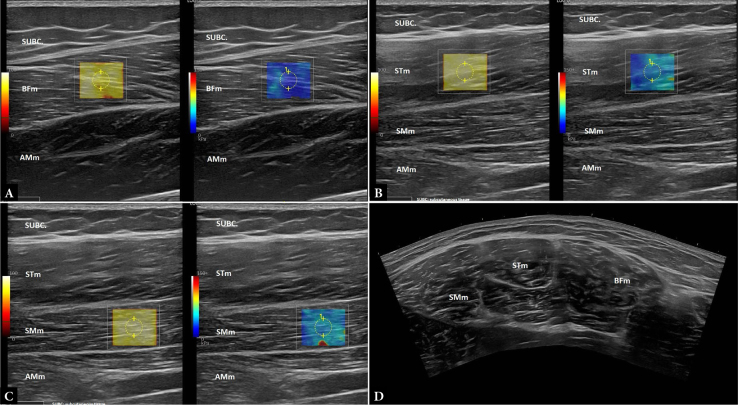

Aim: The Nordic hamstring curl appears effective in reducing the incidence of injury in physically active young adults, likely through its capacity as an eccentric exercise to increase muscle stiffness. Although eccentric exercises have been shown to increase muscle stiffness, medium- and long-term Nordic hamstring curl training programs have not demonstrated an effect on muscle stiffness. This study examined the acute effects of a single session of Nordic hamstring curls on the stiffness of the biceps femoris, semitendinosus, and semimembranosus muscles using ultrasound shear wave elastography, an accepted method for measuring passive muscle stiffness.

Material and methods: Twenty physically active adults (ages 19-27 years) were randomly assigned to either the Nordic hamstring curl group (n = 10) or the control group (n = 10). Shear wave elastography was performed on the dominant kicking leg for both groups. The exact location of the probe was marked to ensure the same area was assessed during post-testing. Both groups performed a 5-minute cycle ergometer warm-up followed by three 30-second standing static stretches. The Nordic hamstring curl group then performed three sets of six repetitions of the eccentric phase of the Nordic hamstring curl with 1-minute rest intervals between sets. All subjects then rested for five minutes before shear wave elastography was performed.